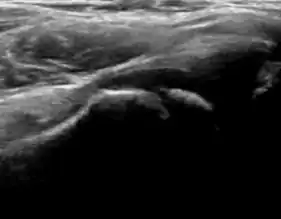

Ultrasound

Ultrasound is the first-choice technique for diagnosis of newborns hip dysplasia. In experienced hands with appropriate technology, ultrasound can also be useful during the first year of life. Some European healthcare systems encourage universal ultrasound screening in neonates between the sixth and eighth weeks. Although it shows higher initial costs caused, it leads to significant reduction in the total number and overall costs of dysplastic hips undergoing operative and nonoperative treatment.[1]

Ultrasound allows categorizing pediatric hips, according to Graf’s criteria, in four main types: normal, immature, and dysplastic (subluxed and dislocated). This classification is based on measurements of the acetabular inclination angle (alpha), cartilage roof angle (beta), and infant age. The femoral head coverage can also be determined by dividing the length of the femoral head covered by the acetabular fossa and the diameter of the femoral head. Its lower normal limits are 47% for boys and 44% for girls (Figure 11).[1]

During childhood, ultrasound is a quick method to assess hip pain and quite often may be used to avoid use of irradiating techniques, such as radiography or CT. Ultrasound allows evaluation of joint effusion, synovial thickening and neovascularity, the bone/cartilage contour, and the femoral head-neck alignment. Although sonography is extremely sensitive in detecting increased synovial fluid, it is nonspecific and cannot be used with accuracy to determine the type of fluid. Transient synovitis of the hip, despite being the most frequent cause of pain in children between 3 and 10 years, remains a diagnosis of exclusion. It usually shows anechoic fluid, but echogenic fluid can also be found. The effusion is considered pathologic when it is measured at >2 mm in thickness. The differential diagnosis is wide, including osteomyelitis, septic arthritis, primary or metastatic lesions, LCPD, and SCFE. Discrimination from septic arthritis is challenging, often requiring joint aspiration. In septic arthritis, US is able to demonstrate a hip joint effusion, synovial thickening, and cartilage damage, although the appearances are nonspecific.[1]

A step between the head and the physis can be detected in children with SCFE, while abnormalities in the femoral head contour may suggest the presence of LCPD. In both cases, radiographs are mandatory to confirm diagnosis and severity (Figure 12).[1]